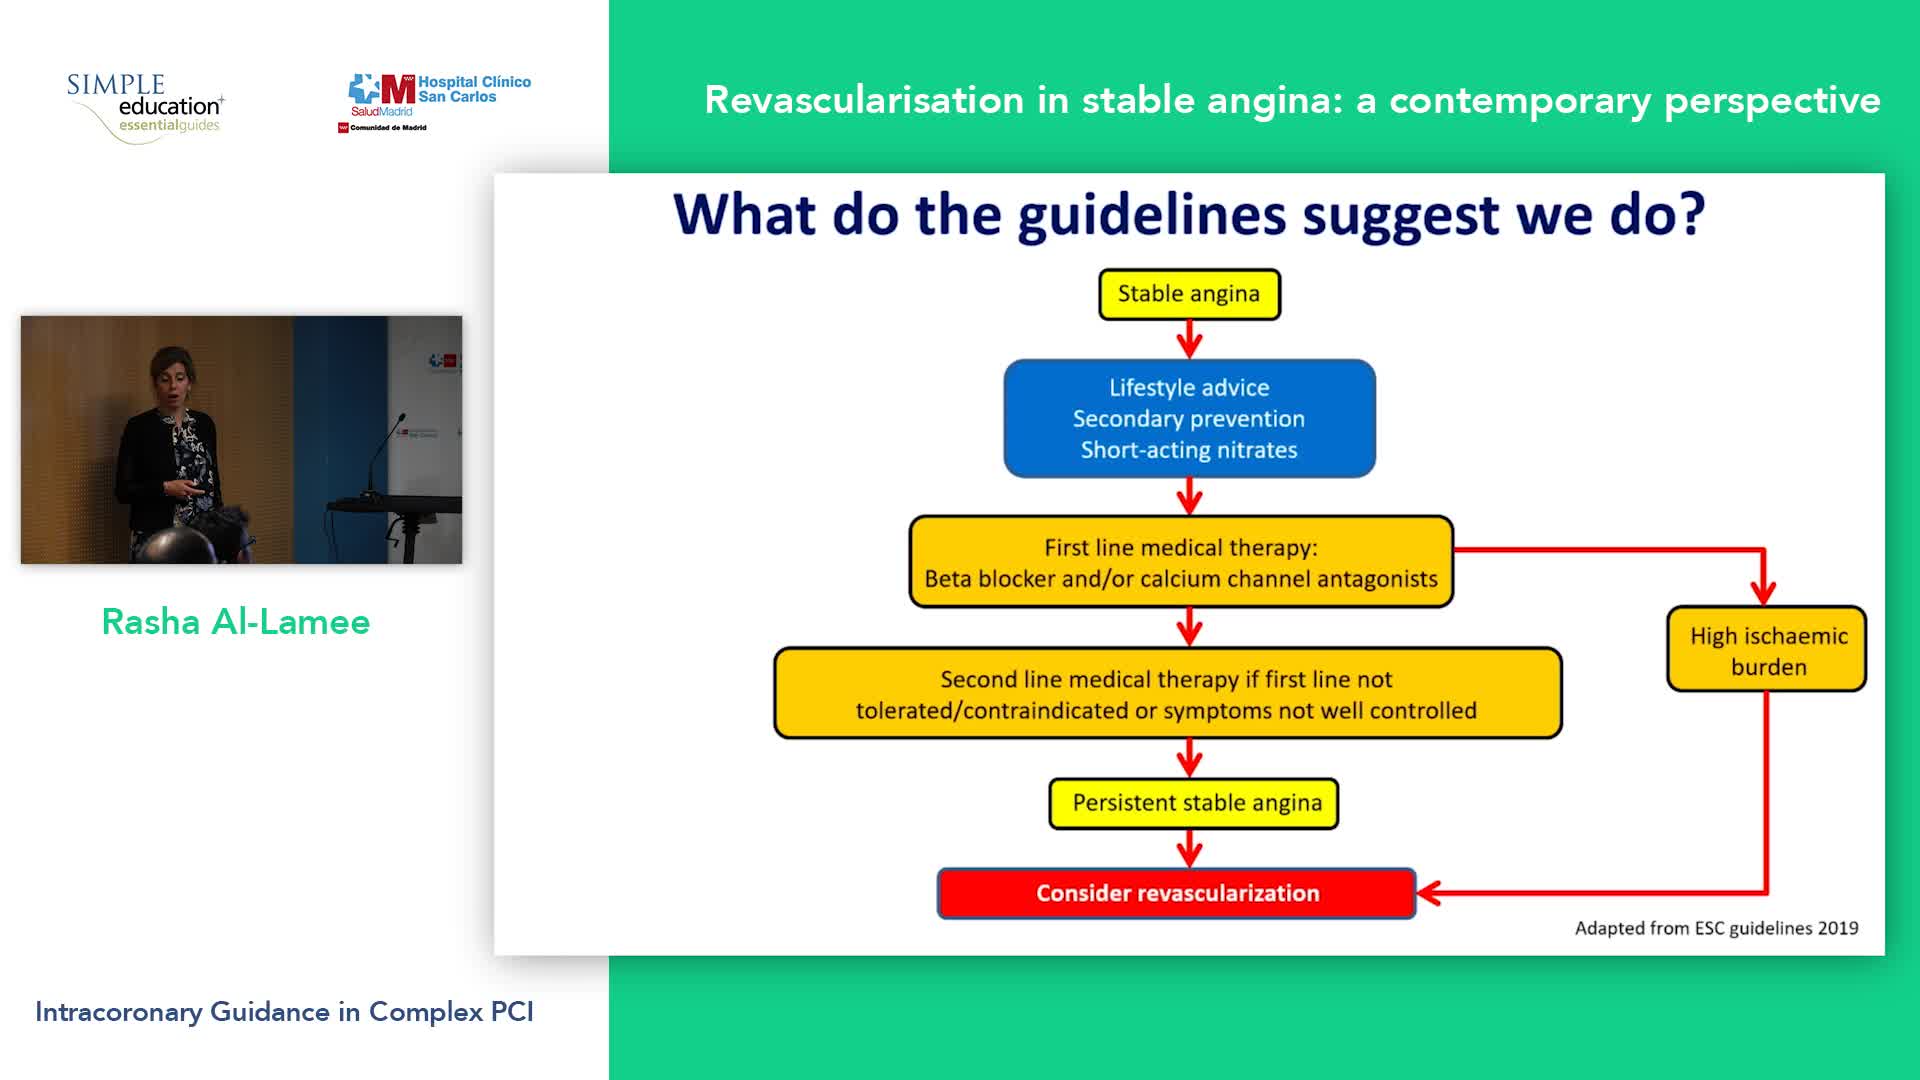

Revascularisation in stable angina: a contemporary perspective - Dr Rasha Al-Lamee

Simple Education